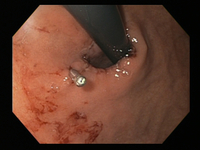

Mallory-Weiss tear

Mallory Weiss tear after application of through-the-scope clip results in hemostasis

From the personal collection of Douglas Adler; used with permission